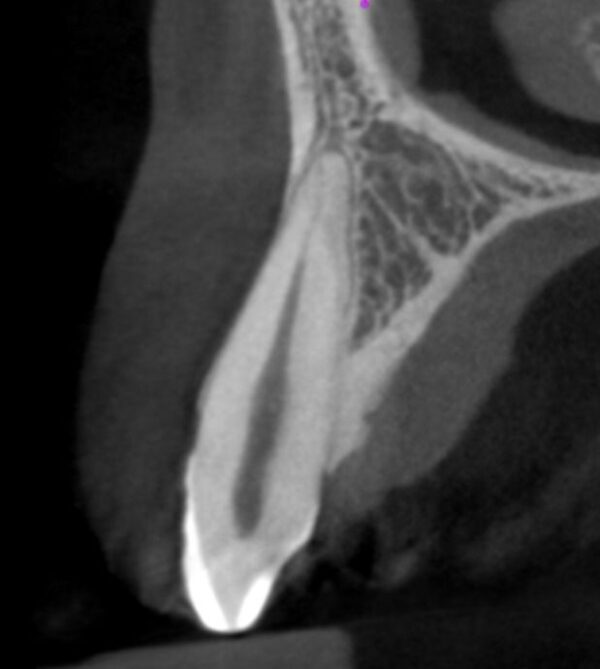

From education.cavendishimaging.com

CBCT Interpretation of Diseased Anatomy Cavendish Imaging Dental Cbct Interpretation • discuss the options in cbct. learn the general principles and protocols for analyzing cone beam computed tomography (cbct) scans in dentistry. learn about the principles and practices for safe and appropriate use of cbct in oral and maxillofacial radiology. learn the fundamentals of radiographic interpretation for dental diagnosis and treatment planning. • describe dental scenarios. Dental Cbct Interpretation.